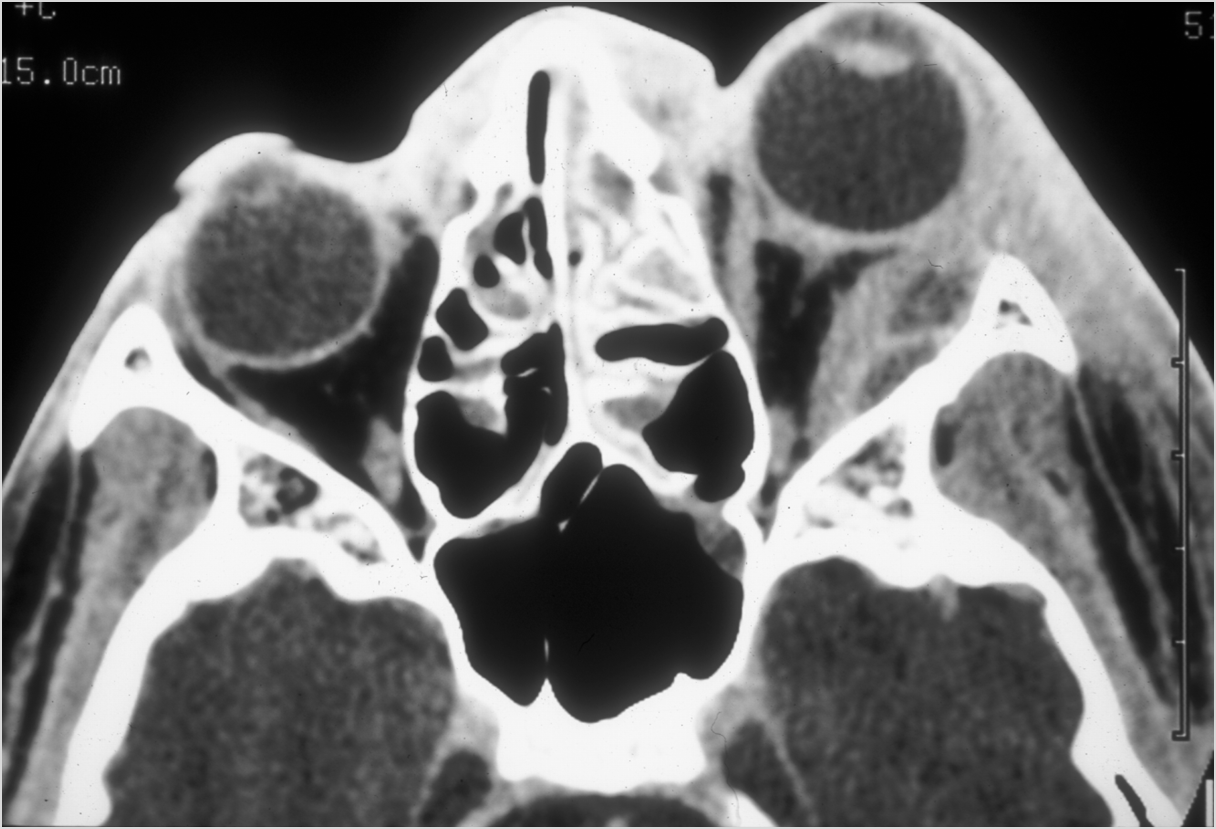

Orbits

The extraconal orbital fat is abnormal. [Yes/No]

There is a subperiosteal abscess or edema along the medial wall, roof or floor of the orbit. [Yes/No]

The extraocular muscles are swollen or otherwise abnormal. [Yes/No]

The intraconal orbital fat is infiltrated. [Yes/No]

The orbital apex and the superior and inferior orbital fissures are infiltrated. [Yes/No]

The superior and/or inferior ophthalmic veins are dilated or thrombosed. [Yes/No]

Proptosis is present. [Yes/No]

The optic nerve is stretched in appearance. [Yes/No]

The posterior aspect of the globe is tented in appearance. [Yes/No]